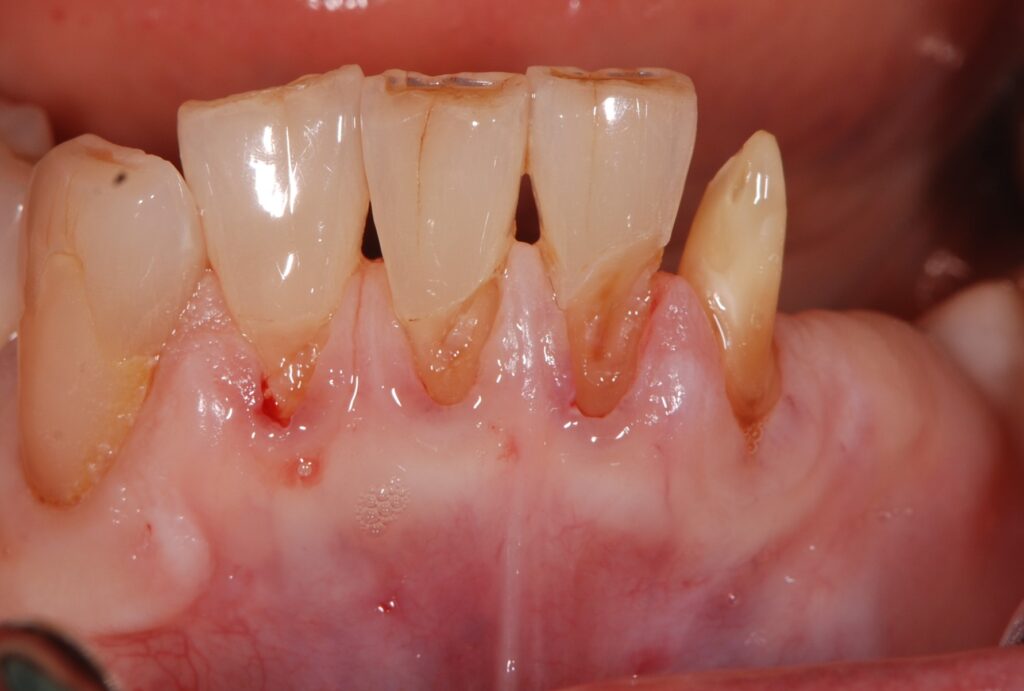

• 治療前

前歯の見た目が気になるし、歯ブラシが当たると痛い。何度も詰め物をやり直しているが、どんどん歯茎が下がっているような気がする。歯茎が下がり、歯の根が露出したところが虫歯になっていた(根面う蝕)。

古い詰め物と虫歯を取った状態。血管が透けて見えるほど薄い歯茎である。このような歯茎は歯ブラシが当たると痛みを感じやすい。